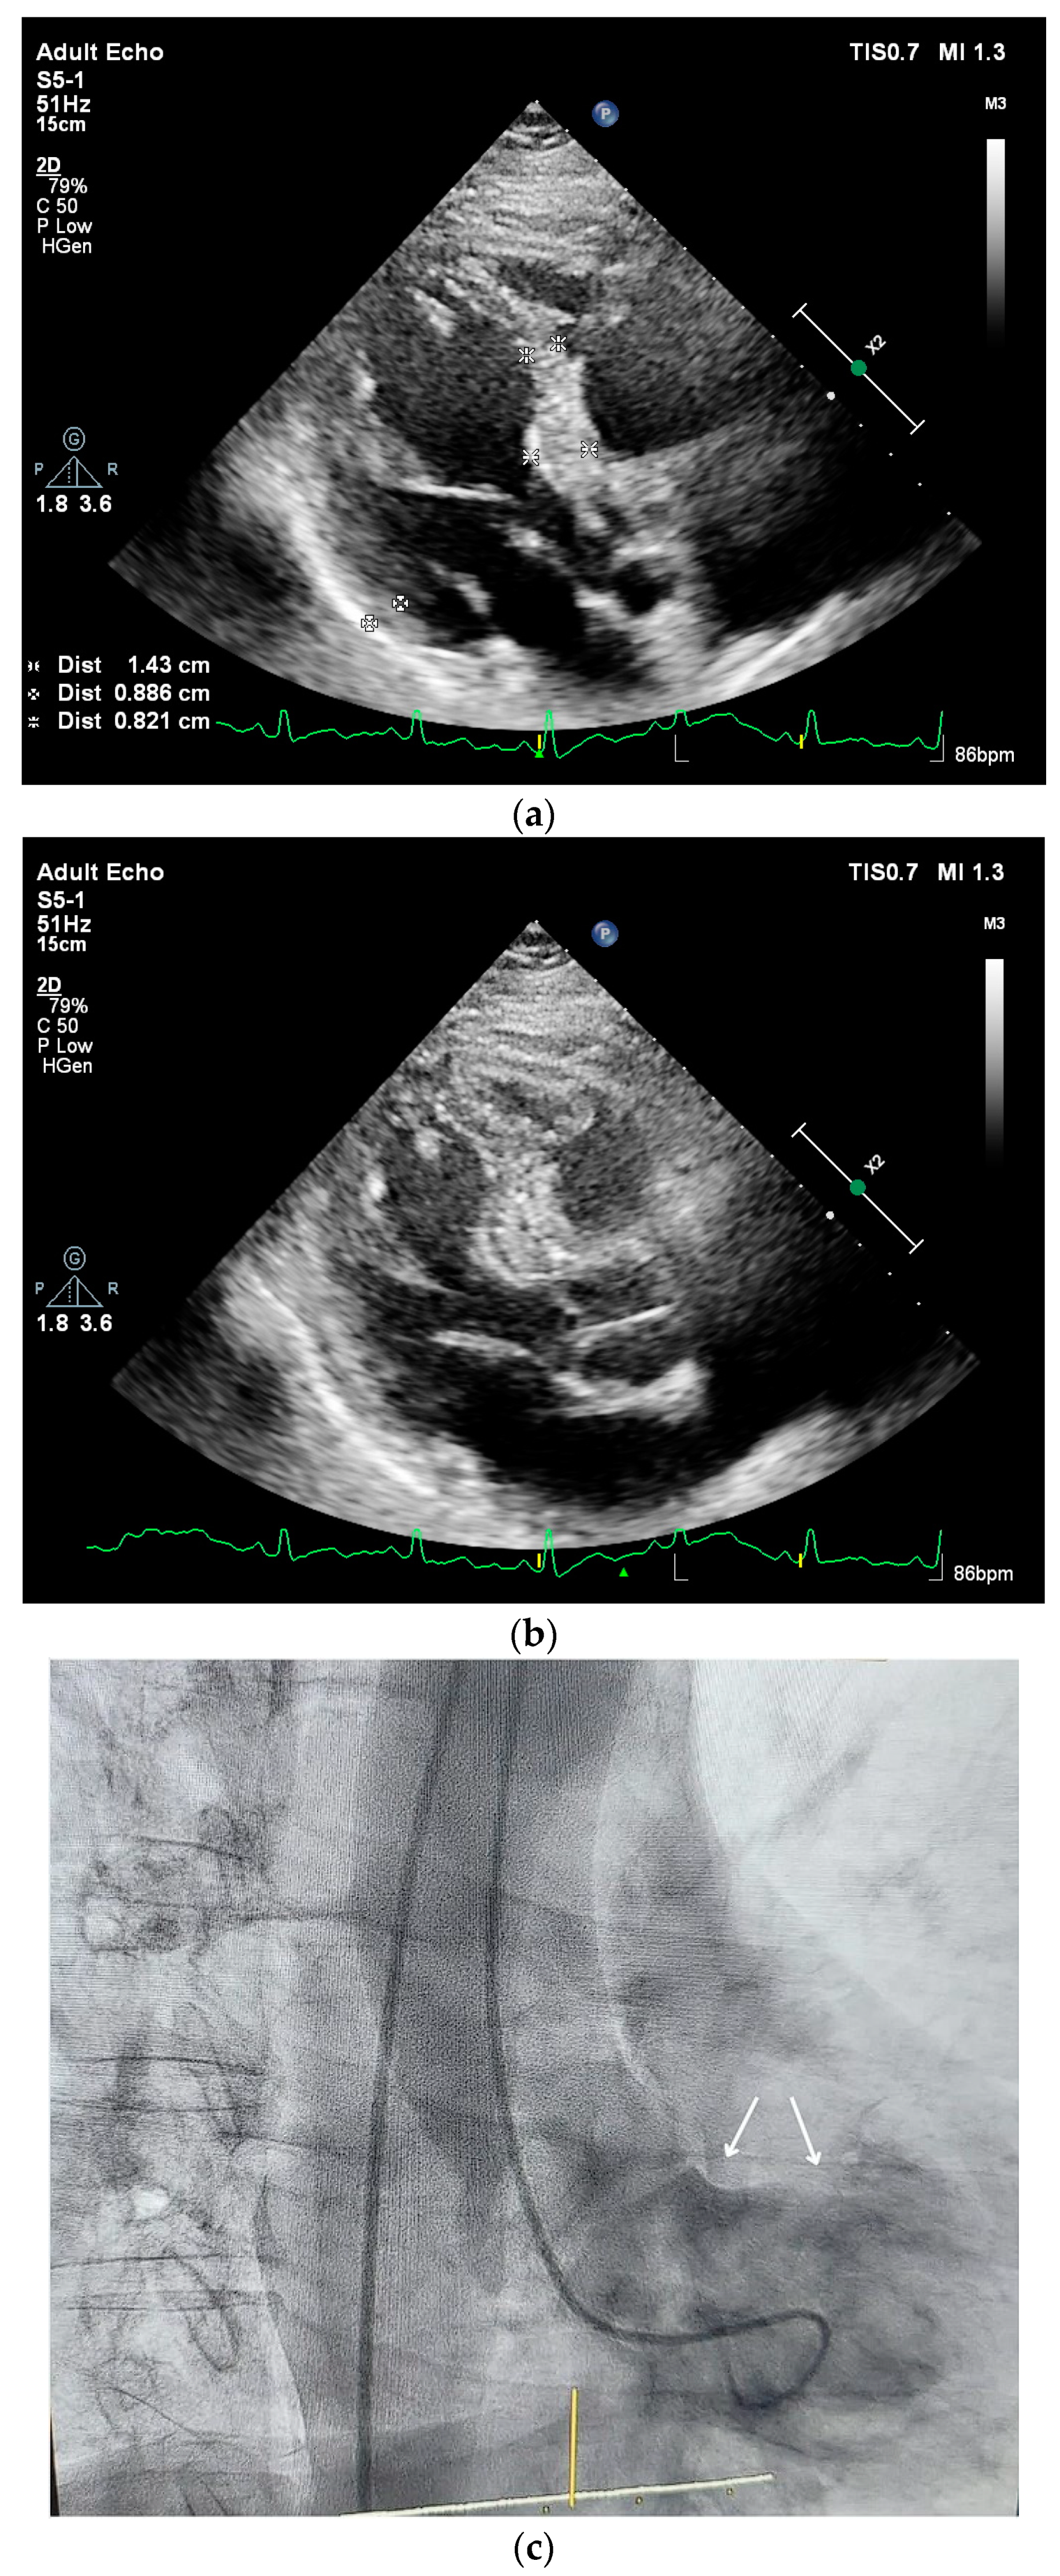

- The effect of superposed multiple stressors is independent from the type of stress and complex SHM with tissue heterogeneity in human beings (Figure 3a–c) having a striking difference from the regular segmental remodeling progression in small animals under stress induction determined by microimaging [12,13,14].